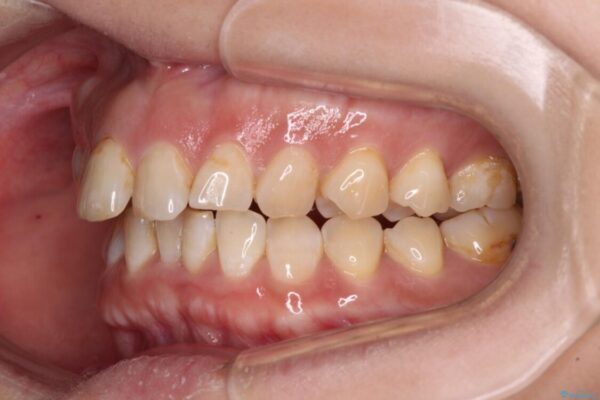

舌の突出癖が原因で上下の歯に大きなスペースが生じていたため、舌のトレーニングをしっかり行っていただくことで、上顎歯列をスムーズに移動させることができました。

治療後

• 【モニター】飛び出た前歯を整えたい ワイヤー矯正治療 治療後画像